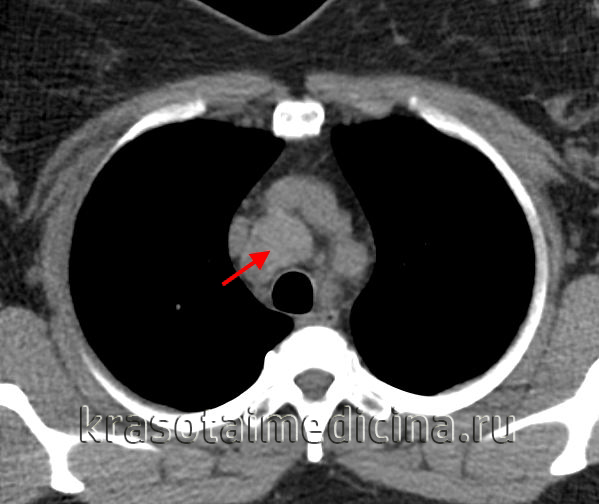

КТ, МРТ при неходжкинской лимфоме лимфоузлов поднижнечелюстного пространства

• Неходжкинская лимфома = злокачественная опухоль лимфоретикулярной системы, которая предположительно происходит из лимфоцитов и их производныхб) Визуализация:

1. Общая характеристика:

• Лучший диагностический критерий:

о Множественные двусторонние увеличенные лимфоузлы сразу в нескольких цепях

• Локализация:

о Может быть поражена любая цепь, в том числе I уровня

• Размер:

о Обычно несколько узлов размерами 1-3 см

о Крупный доминирующий узел может достигать 3-5 см

• Морфология:

о Лимфоузлы округлые или овальные, обычно солидные2. КТ при неходжкинской лимфоме лимфоузлов поднижнечелюстного пространства:

• КТ с КУ:

о Множественные двусторонние округлые лимфоузлы, сразу в нескольких цепях

о Контраст накапливают вариабельно:

- Могут быть изоинтенсивны мышцам, могут эффективно накапливать контраст3. МРТ при неходжкинской лимфоме лимфоузлов поднижнечелюстного пространства:

о При некрозе накапливают контраст по периферии4. Рекомендации по визуализации:

• Лучший метод визуализации:

о КТ с КУ-исследование первой линии

• Протокол исследования:

о В последнее время для оценки распространенности все чаще используют ПЭТ/КТв) Дифференциальная диагностика неходжкинской лимфомы лимфоузлов поднижнечелюстного пространства: